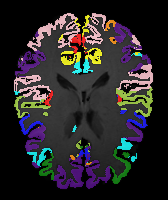

Brain MRI experiment: We also evaluate our method on the MindBooggle101 [4] brain MRIs with 32 cortical regions. We fuse corresponding segmentation labels of the left and right brain hemispheres. MindBoogle101 consists of images from multiple datasets, e.g., OASIS-TRT-20, MMRR-21 and HLN-12. After removing images with incorrect labels, we obtain a total of 85 images. We use 5 images from OASIS-TRT-20 as validation set and 15 as test set. We use the remaining 65 images for training. Manual segmentations in the N=1 and N=21 experiments are only from the MMRR-21 subset; this simulates a common practical use case, where we only have few manual segmentations for one dataset and additional unlabeled images from other datasets, but desire to process a different, new dataset. All images are 1mm isotropic, affinely-aligned, histogram-matched, and cropped to size . We apply sagittal flipping for training data augmentation. We use the same loss weights as for the knee MRI experiment except for , since cross-subject brain registrations require large deformations and hence less regularization.

Results: All trained networks are evaluated using Dice overlap scores between predictions and the manual segmentations for the segmentation network, or between the warped moving segmentations and the target segmentations for the registration network. Tabs. 1 and 2 show results for the knee and brain MRI experiments respectively in Dice scores (%). Fig. 2 shows examples of knee MRI registrations and brain MRI segmentations.

Brain results: Dice scores for segmentation and registration increase by about 2.6 and 3.5 respectively for the cortical structures of the brain MRIs.

One-shot learning: In the one-shot experiments on both datasets, reasonable segmentation performance is achieved; moreover, DA increases the Dice score over unsupervised registration by about 2.7 and 1.8 on the knee and brain data respectively. This demonstrates the effectiveness of our framework for one-shot learning.

Qualitative results: DA achieves more anatomically consistent registrations than the mono-networks on the knee (Fig. 2) and Brain MRI samples (see supplementary material).